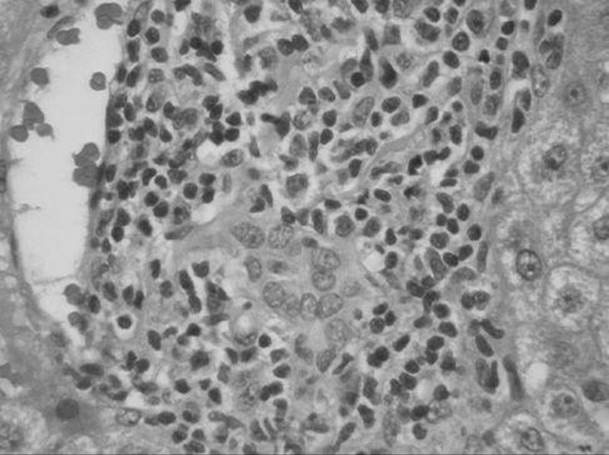

A 46-year-old man who admits to drinking “3 or 4 beers a day” presents with jaundice, right upper quadrant abdominal pain, and fever. A liver biopsy was eventually performed and is shown below. What is the most likely diagnosis?

Figure 51-2

Alcoholic hepatitis. Typical features of alcoholic hepatitis include Mallory’s hyaline, which is an eosinophilic inclusion within hepatocytes that stains with ubiquitin, neutrophils surrounding individual degenerating hepatocytes, sclerosing hyaline necrosis, and steatosis, predominantly macrovesicular.